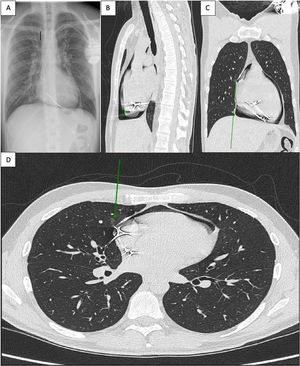

Thirty-eight-year-old patient with previous history of pacemaker insertion one year ago, as consequence of toxic dilated myocardiopathy following chemotherapy for non-Hodgkin lymphoma. After pacemaker placement, a chest X-ray was performed with no immediate complications. One year later he presents to the emergency department with acute chest pain and bubbling sensation during exercise, not previously reported. A chest X-ray was performed showing pneumopericardium (Fig. 1A).

Chest CT scan confirmed the presence of moderate pneumopericardium (Fig. 1B) secondary to pleural and cardiac perforation by pacemaker lead (Fig. 1C and D arrows).